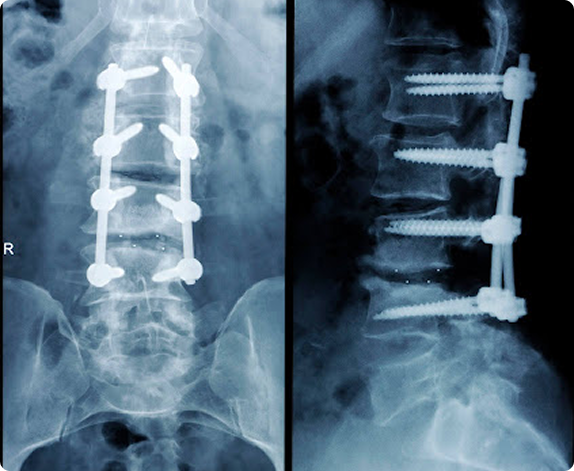

Previous lumbar fusion or surgery increasing SI joint load

Answer: Adjacent levels often wear out faster.

Spinal fusion stabilizes one level but transfers stress to the discs and joints above and below, leading to adjacent segment disease. Scar tissue, muscle atrophy, and nerve irritation can also persist. Nonsurgical options like PRP or radiofrequency treatment can help preserve the surrounding spine.

Lumbar | Post-Surgery | Interventional Spine

Answer: They mean nearby levels or implants break down over time.

After fusion, joints next to the fused area compensate by moving more, sometimes developing arthritis or stress fractures. Hardware fatigue or loosening can also occur years later. Regular imaging helps detect changes early; pain-management injections or strengthening programs can often delay revision surgery.

Lumbar | Cervical | Post-Surgery | Spine Degeneration